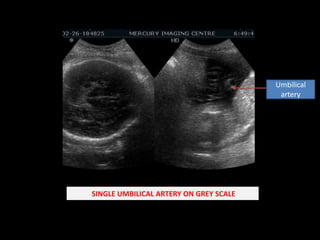

Umbilical artery SINGLE UMBILICAL ARTERY ON GREY SCALE

Umbilical artery SINGLEUMBILICAL ARTERY ON GREY SCALE